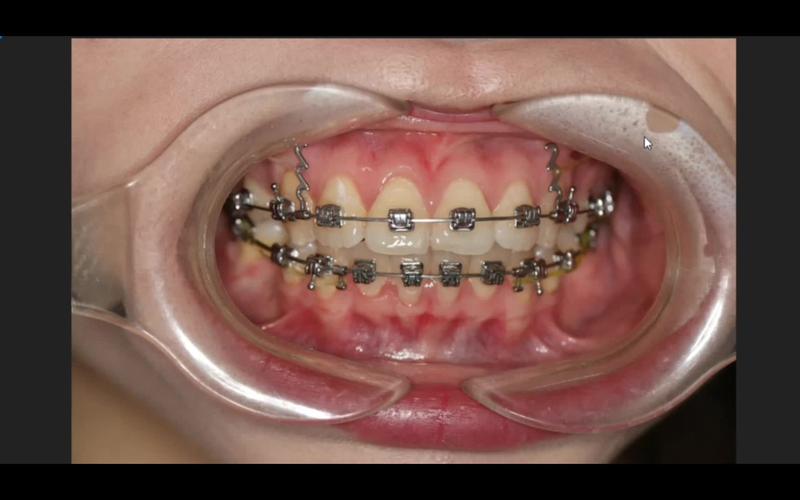

口腔正畸托槽粘贴是正畸治疗中的关键环节,其精准性和稳定性直接影响牙齿移动的效率和最终治疗效果,托槽作为正畸装置中直接与牙齿表面粘接的部分,需承受持续的矫治力,因此粘贴过程需严格遵循操作规范,确保每一颗托槽都位于理想位置,以下将从材料准备、操作步骤、注意事项、常见问题及术后护理等方面详细阐述口腔正畸托槽粘贴的全过程。

托槽粘贴需严格遵循“隔湿-清洁-酸蚀-涂布粘接剂-定位-粘贴-固化-检查”的流程,每一步骤均影响最终效果。

- 粘贴托槽:用托槽镊夹取托槽,对准定位点,轻压托槽底板,去除多余粘接剂(避免刺激牙龈),用探针调整边缘,确保托槽无翘动。

- 光照固化:用光固化灯从不同方向(近中、远中、合面、龈面)照射托槽,每个方向照射10-20秒(总时间≥30秒),确保粘接剂完全固化(注意保护患者眼睛,使用护目镜)。

- 咬合检查:用咬合纸检查托槽是否干扰咬合,若有早接触,用金刚砂针轻轻打磨托槽合面边缘,避免正畸过程中牙合创伤。